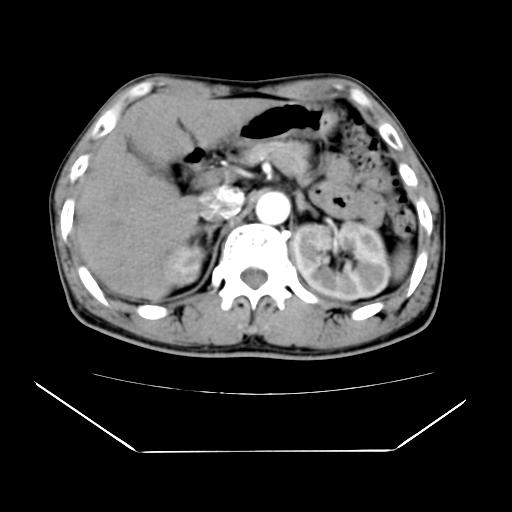

男性,55岁,外院体检afp明显升高,但b超未发现异常,否认乙肝病史。来我院ct增强。有延时扫描。

肝脏右叶动脉期可见低密度影,至延迟期被充填,考虑血管瘤可能性大。

肝右叶病灶

不排除肝右叶肝癌可能。

如果这个是癌灶的话则下腔静脉有瘤栓可能

肝6段血管瘤

血管瘤可能性大。

考虑肝右静脉影。